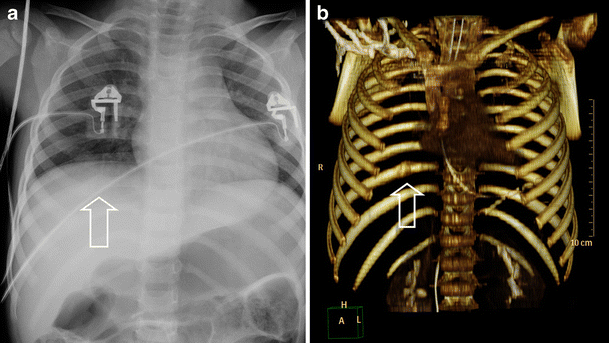

Травма органов грудной клетки на примере клинических случаев

Компьютерная томография (КТ) грудной полости

Мультиспиральная КТ в диагностике тупой торакальной и абдоминальной травмы